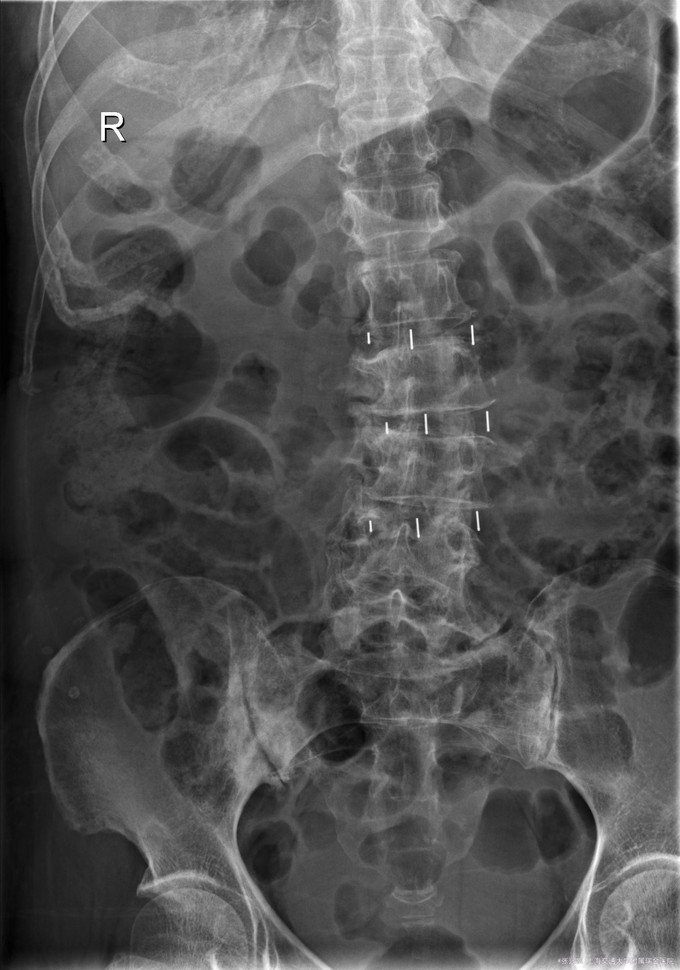

主诉:双下肢麻木7年,腰部酸痛无力 现病史:女性患者,70岁,患者诉腰背无力十几年,约于7年前无明显诱因下出现下肢麻木,站立位加重。后出现腰臀部僵硬,弓背加重,行走距离较短, 不足百米,几年前外院检查诊断为腰椎管狭窄,具体不详。

查体:侧弯畸形,右臀部及右下肢麻木疼痛,腰部活动受限,难以站立。右侧支腿抬高试验50°。双下肢肌力肌张力可。 辅助检查: 磁共振:L1-5,L5-S1腰椎椎间盘突出,腰椎退变,腰椎侧弯

诊断: 腰椎侧弯,腰椎间盘突出 治疗:1期微创侧路椎体融合术+2期 微创后路经皮内固定术

患者侧路微创术后神经压迫症状减轻,腰椎矢状位及冠状位腰椎力线得到改善,戴支具术后可早期下床活动,术后2周后行后路固定手术。